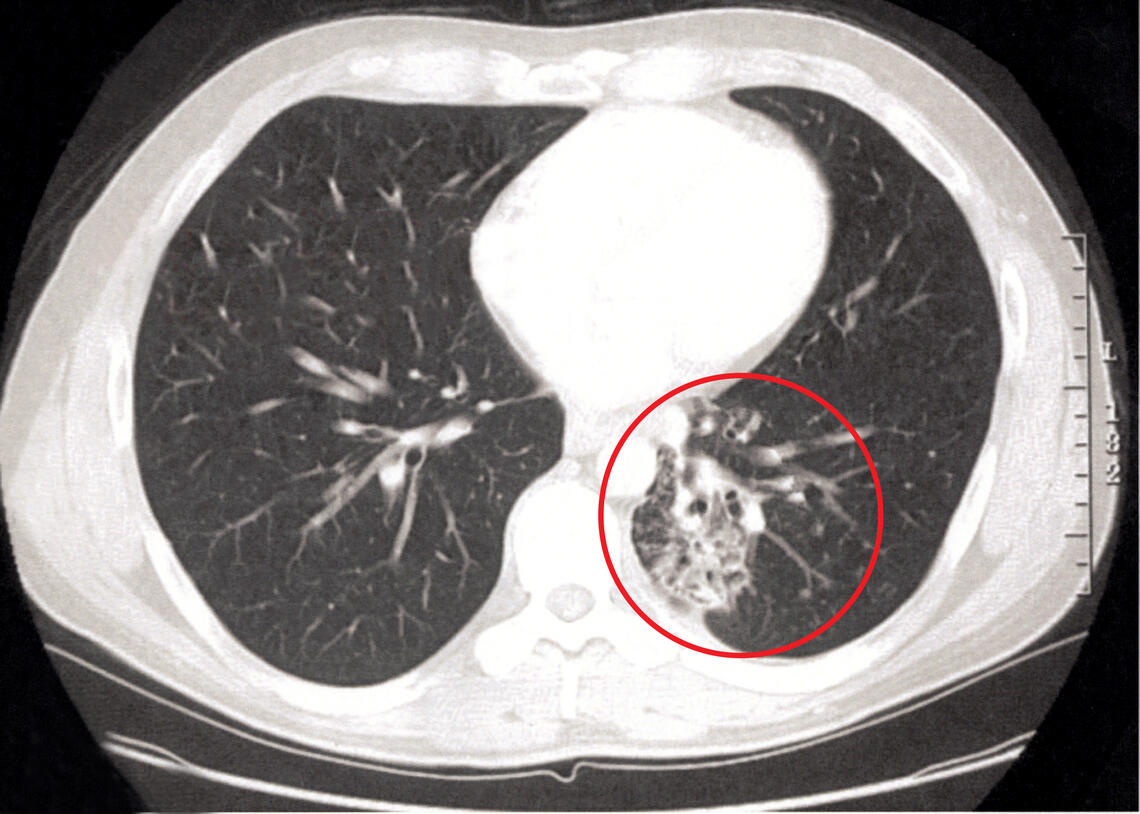

Twenty years ago Clark Spencer was diagnosed with a serious, life-threatening and incurable fungal lung infection he picked up while living in the southern U.S.

Twenty years ago, he was diagnosed with a serious, life-threatening and incurable fungal lung infection he picked up at the age of 38 while living in the southern U.S. After Spencer moved back to Canada, his Calgary medical team started him on a new treatment plan backed by Snyder Institute research and helped him regain lung function.

“When I was first diagnosed, I didn’t think that I was going to make it past 45. So, I owe being here to the care that I received and the research behind it,” he says.

Spencer has now been able to return to doing the things he loves — like spending time with his wife Shelly and walking his dog Kona.